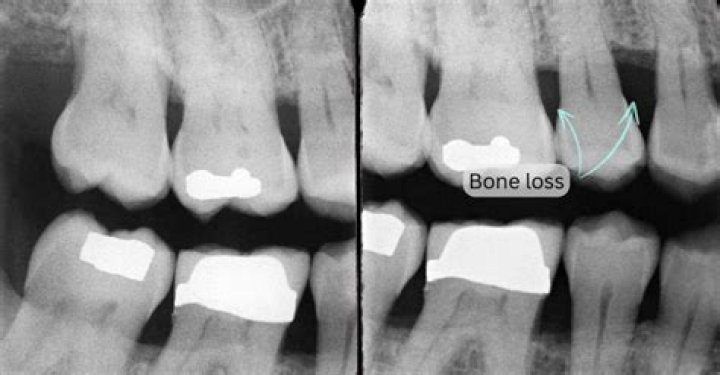

Why am I losing bone in my teeth?

The most common cause of bone loss is tooth loss left unreplaced, especially multiple teeth. Jawbone is preserved through the pressure and stimulus of chewing. When that is removed through tooth loss, the bone “resorbs” (reabsorbs) into the body.